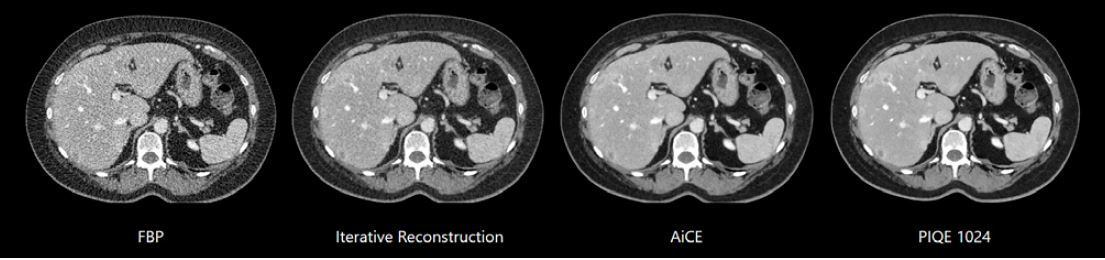

Зображення черевної порожнини, реконструйовані за допомогою різних алгоритмів реконструкції на зрізах товщиною 0,5 мм

Завдяки вдосконаленій технології глибокого навчання (DLR) Aquilion ONE / INSIGHT Edition доктор Рассел Булл бачить значне покращення якості зображення.

«Зображення набагато менш шумні та мають менше артефактів. Ми отримуємо кращі зображення,

але без збільшення дози опромінення», – сказав він. «Загалом реконструкція глибокого навчання була дуже добре сприйнята нашими радіологами. Aquilion ONE / INSIGHT Edition використовує два типи DLR, один із яких Advanced intelligent Clear-IQ Engine (AiCE), який ми зазвичай

використовуємо при скануванні тіла, і Precise IQ Engine (PIQE), який ми зазвичай використовуємо, на даний, момент для коронарних артерій, але також доступний для обстеження

тіла».

«Перевага PIQE 1024 полягає в тому, що він дає нам набагато вищу просторову роздільну здатність без збільшення дози радіації. Оскільки це покращує просторову роздільну здатність, ми можемо отримати зображення коронарних артерій з кальцинатами та стентами зі зменшенням артефактів від них. Ми працюємо на цьому апараті всього 5 тижнів, але ми набагато впевненіші в діагнозі, оскільки роздільна здатність набагато вища», – додав він.

Зображення черевної порожнини з PIQE 1024 товщиною зрізу 0,5 мм демонструють підвищену просторову роздільну здатність у цього пацієнта з ураженням печінки.

Precise IQ Engine (PIQE)

Це алгоритм реконструкції

глибокого навчання, який

максимізує власну роздільну

здатність комп’ютерної

томографії для отримання

матричних зображень

суперроздільності 1024.

Зображення PIQE показують

чіткіші анатомічні деталі

для кращого окреслення

невеликих анатомічних

структур для більш точного

діагнозу.